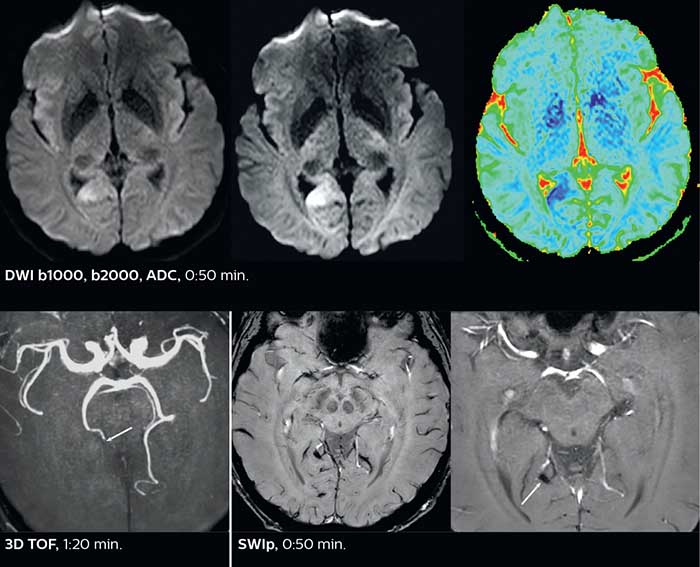

Comprehensive stroke MRI within acceptable time

Dr. Savatovsky appreciates the improvements and flexibility that Elition with Compressed SENSE and MultiBand SENSE provides, particularly for stroke patients. “For stroke, it allows us to cut about 5 minutes off of our stroke protocol, or to keep the same acquisition time and get more insights.” The ability to perform more sequences can help in making a swift and confident diagnosis. “For example, our stroke cases usually include the regular sequences that every center does (b1000 diffusion, FLAIR, time-of-flight angiography), but we also image supra aortic vessels, and we can replace a gradient echo sequence with a fast 50-second susceptibility-weighted sequence, and all of this doesn’t add much time. because all the regular sequences are accelerated on Elition.” “The time savings with Compressed SENSE and MultiBand SENSE make it easier to add sequences to give us additional insights. Depending on the context and the first results, we might add a DSC perfusion to assess the ischemic penumbra, an ASL perfusion to help find an alternative cause in case of normal diffusion, or add a high-resolution T1 sequence for a stroke patient, to quickly assess wall imaging in emergency cases. The additional sequences can help improve patient management, because we can already consider some alternative diagnoses if the morphological MRI is normal.”

Improved diffusion imaging in stroke patients

Using MultiBand SENSE allowed the staff to improve their diffusion quality. “Our diffusion sequence was already fast before, about 40 seconds. Now with Elition, it still lasts 40 seconds, but we improved the spatial resolution by 0.2 mm and use high b-values to be more sensitive to visualize changes related to acute stroke,” says Dr. Savatovsky. “We now also developed a high resolution DTI sequence (1.3 x 1.3 x 2 mm) that can be reformatted and takes 2 to 5 minutes depending on the coverage. We use it every time we have a doubt, or when we expect the diffusion to be abnormal but don’t see that on the fast sequence. We occasionally spot small ischemic infarctions that would not have been visible with the regular diffusion sequence.”

This is an example of acute ischemic stroke with distal occlusion of the right posterior cerebral artery. Note the improved visibility of the ischemic territory on the diffusion weighted image with high b-value. The 3D FLAIR shows a distal PCA occlusion. The fast SWIp depicts the thrombus on the isolated second echo image. The total scan time (including SmartBrain, preparations and a fast 3D T1w TSE Gd) is 8:00 minutes.